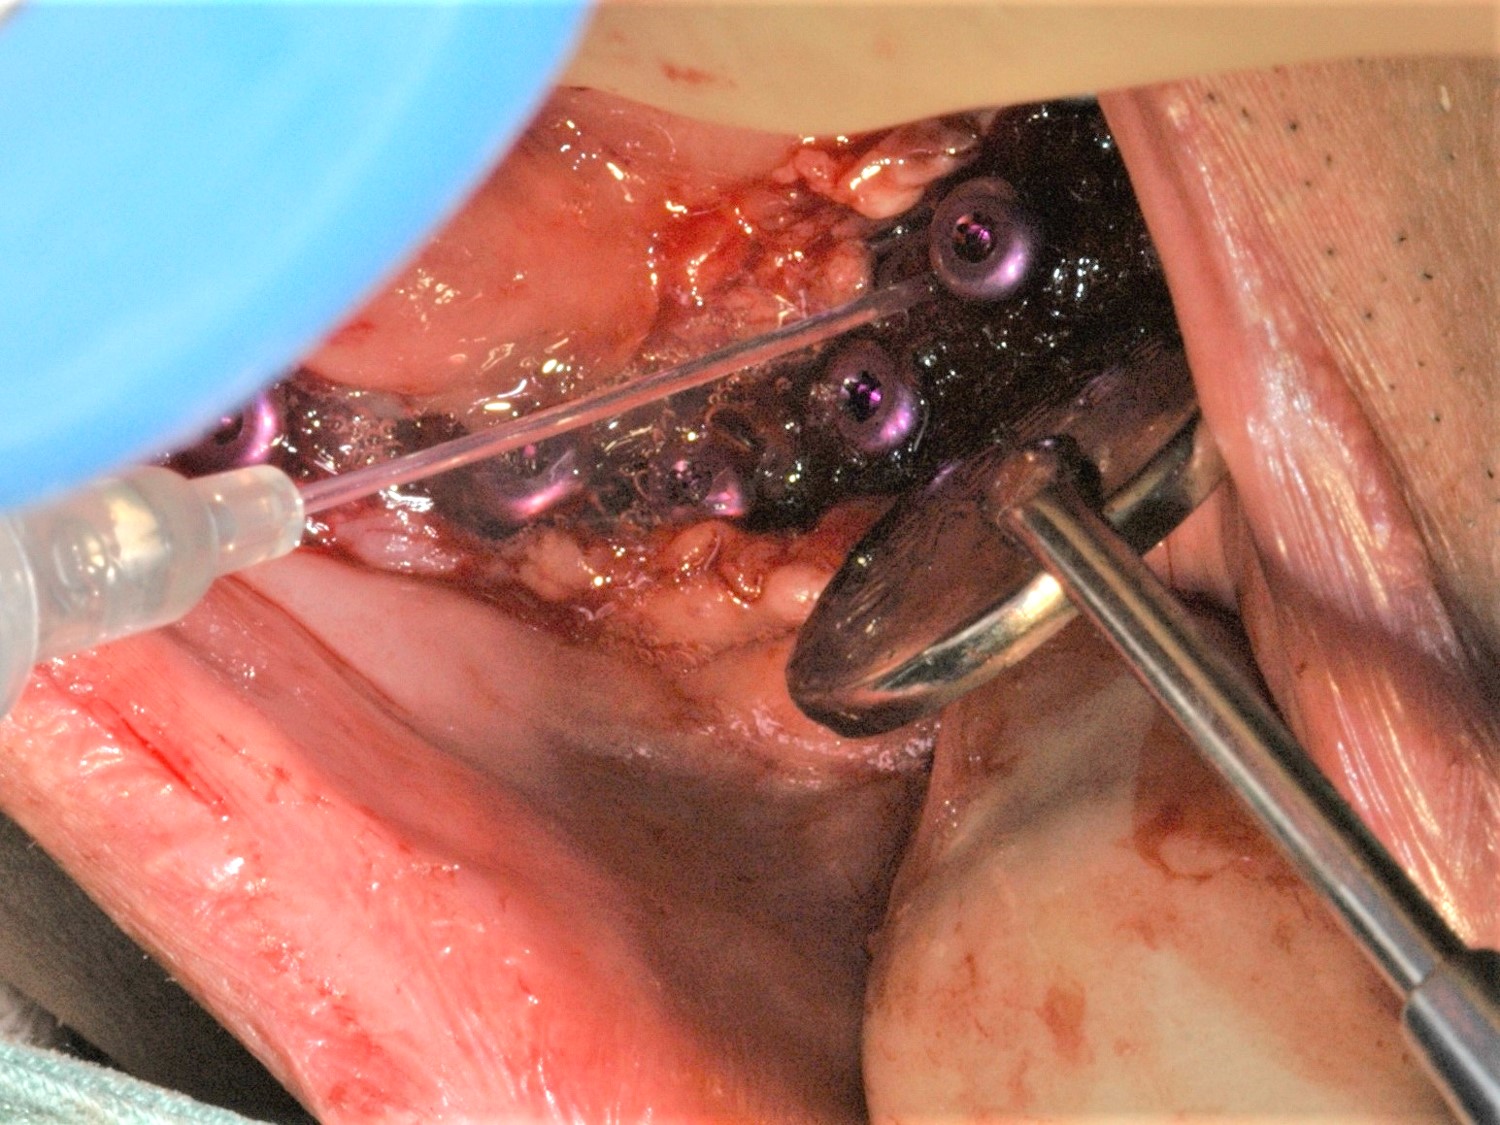

インプラント埋入から2か月後、インプラント周囲に歯槽提の固有歯肉を作成するために粘膜再生の手術を行った。口蓋より口蓋粘膜を移植することも考えたが、患者さんの負担が増えることと広範囲であり口蓋の粘膜をかなり広範囲で切除しないといけなくなることから、吸収性ポリグリコール酸フェルト ネオベール シートタイプ ネオベール(GUNZE)とベリプラスト 血漿分画製剤(生理的組織接着剤) フィブリノゲン加第XIII因子 を用いた再生法を選択した。なお、ペリプラストは血液製剤になるのでその旨、患者さんに説明し、十分な同意を得た上で使用した。

歯槽提の固有歯肉を作成するために粘膜再生手術。ヒーリングアバットメントを装着してネオベールとベリプラスト を付与している。